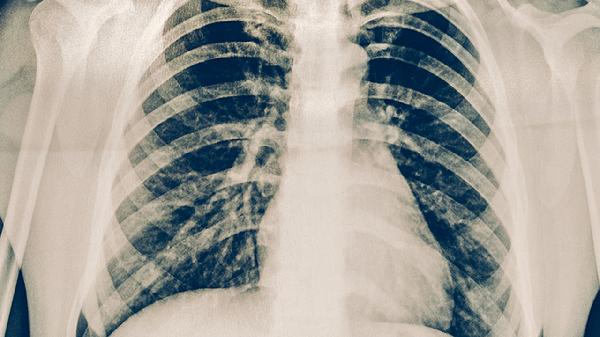

治療期間需通過痰涂片、胸部CT等評(píng)估療效,部分患者因交通不便或懼怕輻射拒絕復(fù)查。這可能導(dǎo)致藥物方案調(diào)整滯后,無法及時(shí)發(fā)現(xiàn)支氣管結(jié)核等并發(fā)癥。強(qiáng)化期應(yīng)每1-2個(gè)月復(fù)查痰菌,鞏固期每3個(gè)月進(jìn)行影像學(xué)檢查。痰菌持續(xù)陽(yáng)性者需進(jìn)行結(jié)核分枝桿菌培養(yǎng)及藥敏試驗(yàn),排除耐藥可能。